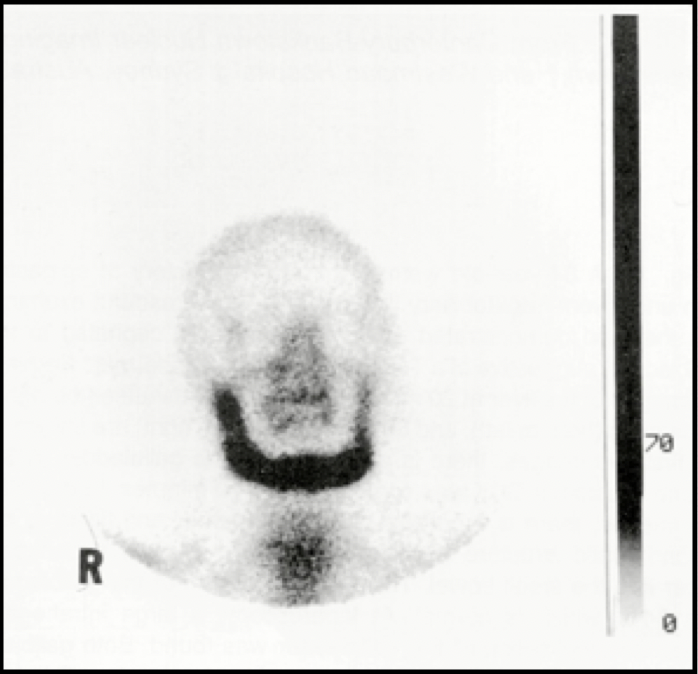

Osteoporosis circumscripta

Image

• A characteristic rim of increased uptake borders the lesion.

• Lytic phase/lesion involving skull bones